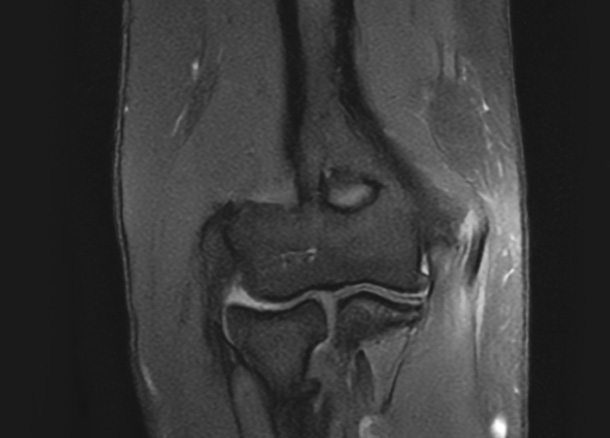

After 수술 후

1년 후 완전 정상화

* 환자에게 받은 소중한 자료입니다.